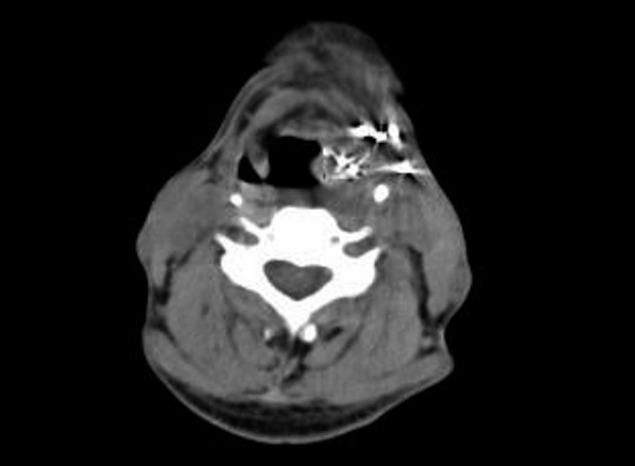

(125)I seeds implant procedures were performed under computed tomography for 34 patients with advanced hypopharyngeal carcinoma. We observed the local control rate, overall survival, and acute or late toxicity rate.

In the 34 patients (stage III, n=6; stage IV, n=28), the sites of origin were pyriform sinus (n=29) and postcricoid area (n=5). All patients also received one to four cycles of chemotherapy after seed implantation. The post-plan showed that the actuarial D90 of (125)I seeds ranged from 90 to 158 Gy (median, 127 Gy). The mean follow-up was 12.3 months (range, 3.4 to 43.2 months). The local control was 2.1-31.0 months with a median of 17.7 months (95% confidence interval [CI], 13.4 to 22.0 months). The 1-, 2-, and 3-year local controls were 65.3%, 28.6%, and 9.5% respectively. Twelve patients (35%) died of local recurrence, fourteen patients (41%) died of distant metastases, and three patients (9%) died of recurrence and metastases at the same time. Five patients (15%) still survived to follow-up. At the time of analysis, the median survival time was 12.5 months (95% CI, 9.5 to 15.4 months). The 1-, 2-, and 3-year overall survival rates were 55.2%, 20.3%, and 10.9%, respectively. Five patients (15%) experienced grade 3 toxic events and nine patients (26%) have experienced grade 2 toxic events.